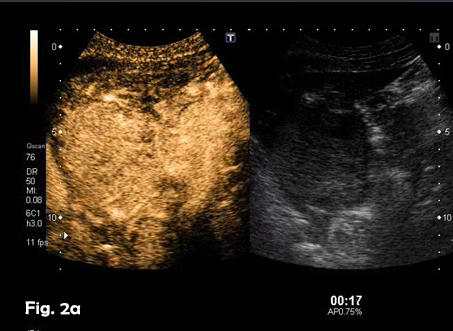

A previously healthy 39-year-old male was referred because of a hepatic mass, found incidentally He was a professional sportsman and regularly participated in competitions. He had taken anabolic steroids for 6-8 weeks two or three times per year from 24 – 32 years old approximately. The remainder of the medical history was unremarkable. Laboratory results showed a slight elevation of ALT and AST with normal bilirubin and alpha-fetoprotein levels. Physical examination was otherwise normal. An abdominal ultrasound showed a well-defined 8.5 x 7.7 cm heterogeneous mass with a hypoechoic peripheral halo in the left lobe of the liver, segments 2 and 3 (Fig 1). A small nodule-in-nodule appearance was evident within the mass as well as some vascularity on colour Doppler. Following the administration of an ultrasound contrast agent (SonoVueTM), the mass showed homogeneous hyper-enhancement in the arterial phase (Fig 2a) (video 1), with wash-out in the late phase in only part of the lesion (video 2), specifically, the nodule-in-nodule appearance area (Fig 2b). These appearances were suggestive of a hepatocellular adenoma with areas of malignant transformation and this was confirmed by both ultrasound guided fine-needle aspiration cytology (video 3) and subsequent histological examination of the surgically resected tumour.

Figure 2:Contrast-enhanced ultrasound (CEUS) in the arterial (a) and late (b) phase. CEUS showed early hyperenhancing features in the arterial phase of the lesion and clear wash out in the small nodule-in-nodule appearance without wash out in the rest of the lesion.

![Hepatic adenoma with focal hepatocellular carcinoma</br> [Aug 2016]](http://s834315022.websitehome.co.uk/wp-content/uploads/2020/11/cotm_august2016_fig02b.jpg)